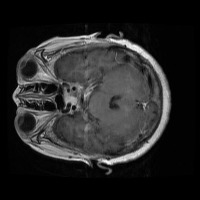

tumor otak Computer Vision Project

Medical Diagnostics: This model can be used for assisting healthcare professionals in diagnosing brain tumors by classifying them into glioma, pituitary, or meningioma, which can save time and lead to early and accurate disease diagnosis.

Training medical students and resident doctors: The model can be used as a training tool for medical students and resident doctors to better understand and identify different types of brain tumors from MRI images.